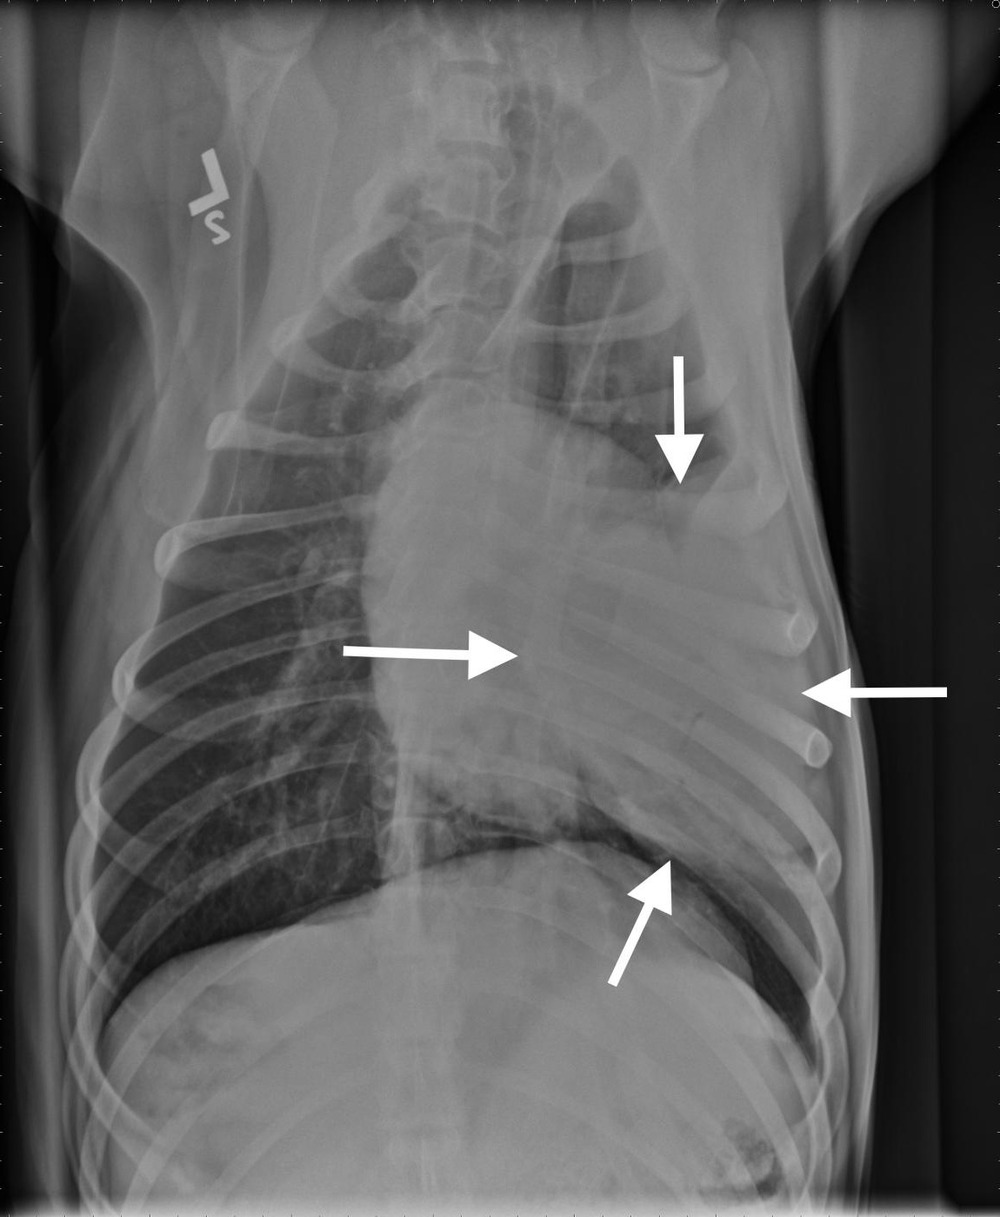

Diagnosis usually happens in layers. A vet will start with a physical exam and history, then move to imaging. Chest X-rays are often the first step, and they can show lung masses, changes in lung pattern, and sometimes enlarged lymph nodes.1, 7

A CT scan can provide a much clearer map of what is happening in the chest, including the size and location of a mass, whether lymph nodes look involved, and whether there are multiple lesions that might suggest spread.1, 7

Because many lung lesions are metastatic, and because primary lung tumours can spread, vets often recommend “staging” tests. This can include blood and urine tests, more detailed chest imaging, and sometimes an abdominal ultrasound to look for a primary tumour elsewhere or signs of spread.1, 7